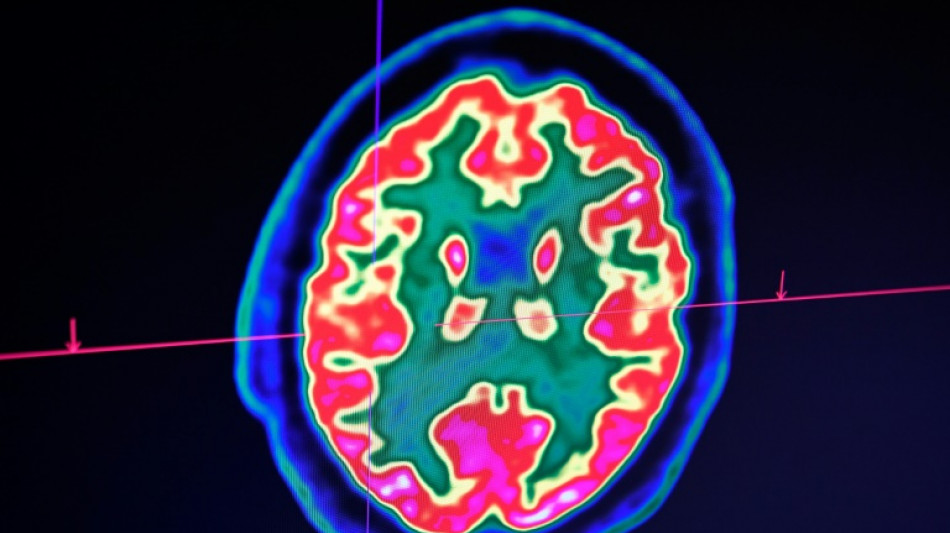

Cancer du cerveau: la guérison d'un enfant ouvre de grands espoirs pour la recherche / Photo: © AFP

Rare mais fatal, le gliome infiltrant du tronc cérébral est l'une des formes les plus redoutables des cancers du cerveau pédiatriques. Un enfant, pourtant, semble défier les statistiques: sa guérison, unique au monde, suscite aujourd'hui de grands espoirs pour la recherche.